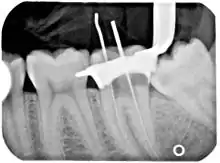

An x-ray of a root canal operation

Filling the root canal

The standard filling material is gutta-percha, a natural polymer prepared from latex from the percha tree (Palaquium gutta). The standard endodontic technique involves inserting a gutta-percha cone (a "point") into the cleaned-out root canal along with a sealing cement.[24] Another technique uses melted or heat-softened gutta-percha which is then injected or pressed into the root canal passage(s). However, since gutta-percha shrinks as it cools, thermal techniques can be unreliable and sometimes a combination of techniques is used. Gutta-percha is radiopaque, allowing verification afterwards that the root canal passages have been completely filled and are without voids.